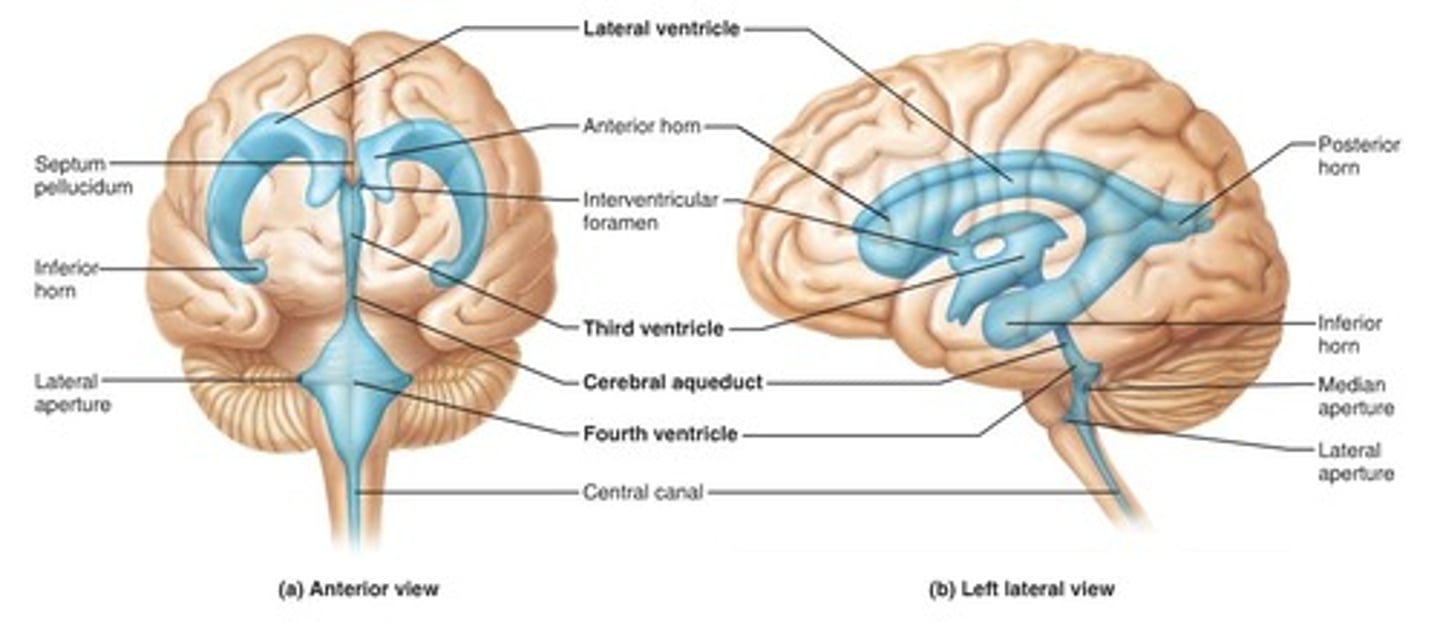

ventricles

cavities in the brain. Includes lateral ventricles - right and left, third ventricle, fourth ventricle, cerebral aqueduct, and choroid plexus.

lateral ventricles (left and right)

right and left. Actual open space. Behind the corpus collosum.

- Cerebrospinal fluid circulates through these ventricles and underneath the meninges.

- Gives the brain buoyancy.

- brain floats a little bit and this prevents trauma.

third ventricle

in the area where the hypothalamus is.

fourth ventricle

located beneath the arbor vitae in the cerebellum.

cerebral aqueduct

connector between third and fourth ventricle in front of colliculi.

choroid plexus

ependymal cells - line ventricles and central canal of spinal cord.